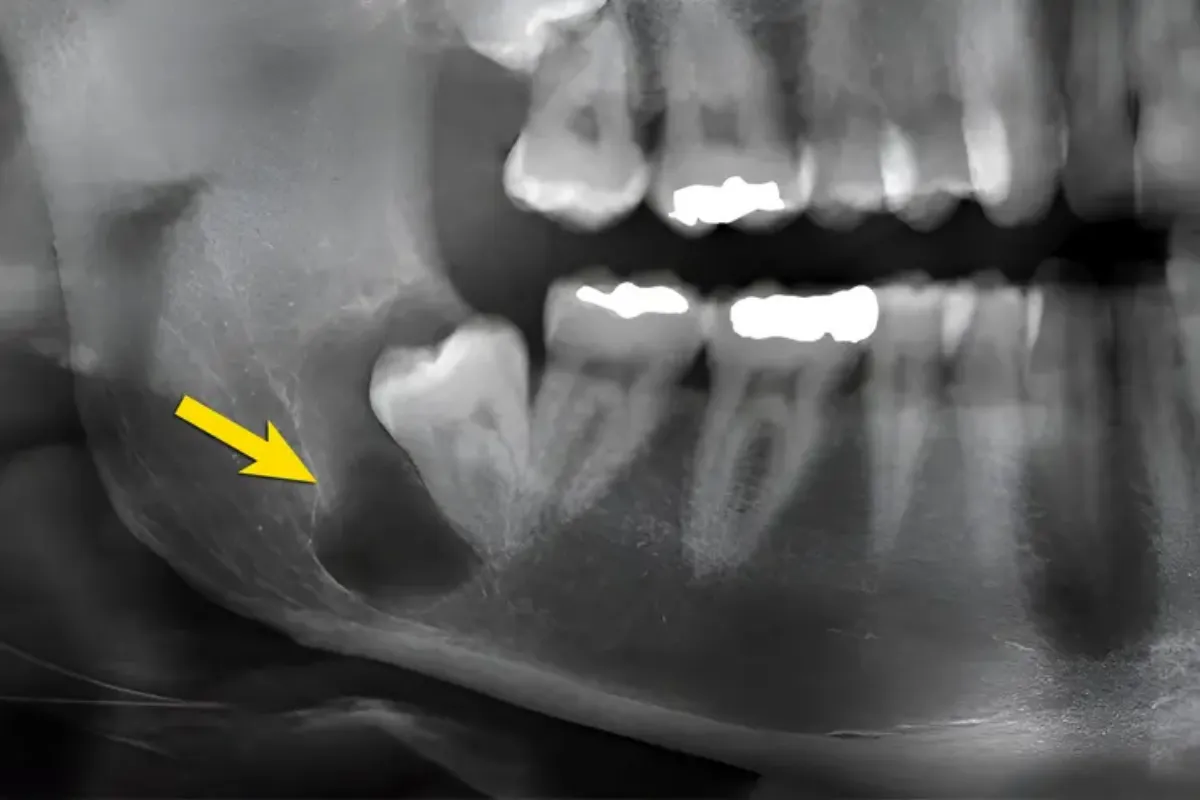

در برخی کودکان، کیست در اطراف دندانی ایجاد میشود که هنوز بهطور کامل رویش پیدا نکرده است. این نوع کیست دندان کودک اغلب بدون درد است و فقط در عکس رادیولوژی دیده میشود. اگر بهموقع تشخیص داده نشود، میتواند باعث تأخیر در رویش دندان دائمی یا جابهجایی آن در فک شود.

تشخیص قطعی کیست دندان کودک تنها با معاینه ظاهری امکانپذیر نیست. دندانپزشک کودک با استفاده از تصویربرداری رادیولوژی، محل، اندازه و ارتباط کیست با دندانهای شیری و دائمی را بررسی میکند. این مرحله برای انتخاب روش درمان ضروری است.